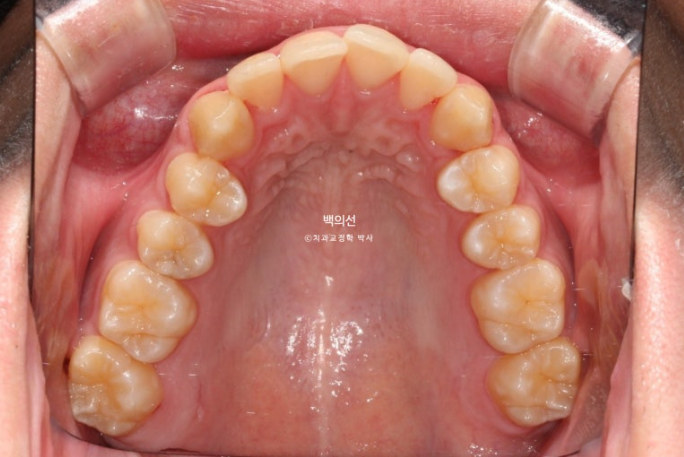

해외에서 4개월간 인비절라인라이트 장치 14개를 일주일씩 교체해가며 모두 낀 후 여름방학때 내원한 모습입니다.

25.07

어금니 교합이 약간 뜨는 부분들이 있습니다.

앞니 배열은 좋아졌습니다.

인비절라인 라이트는 미진한 부분이 있을경우 1회의 추가장치 제작이 가능하지만, 추가장치 없이 마무리하는 경우도 많습니다.

이 경우도 굳이 추가장치 재제작 없이도 마무리가 가능한 상황

약 한달간의 교합 안정화 기간을 거쳐 8월, 치료를 마무리 했습니다.

25.08

교합은 물샐틈이 없습니다.